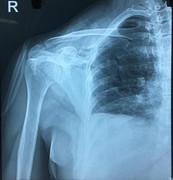

Bệnh nhân mang nhóm máu O Rh(-) rất hiếm bị dao đâm thấu ngực mất nhiều máu nguy kịch may mắn được bác sĩ cứu sống.